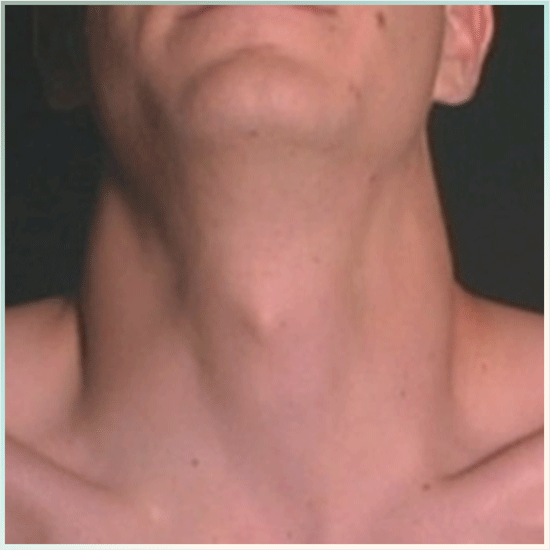

림프조직이 많이 분포된 목이나

겨드랑이와 같은 곳에서 생기는

첫번째로 호지킨 림프종 증상으로는

종양이 발생한 위치가 비대해지면서

부풀어오르는 것입니다.

처음에 통증은 없지만 한눈에

알아볼 정도로 종양이 커지는 형태기 때문에,

이 악성종양이 목에 발생하는 경우에는

기관지를 누르게 되고 통증과 기침이

뒤따를 수 있어요.

림프절이 집중된 부분들이 비대해지는 현상